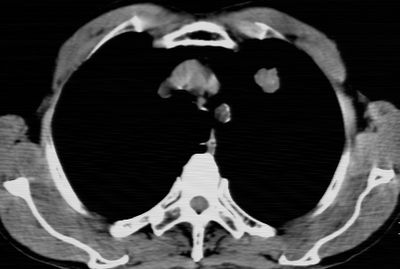

标题: CT24783:m71,既往肺心病史3年,现咳嗽,憋喘。 [打印本页]

标题: CT24783:m71,既往肺心病史3年,现咳嗽,憋喘。

1、左肺上叶spn,毛刺+分叶+血管集束征,考虑周围型肺癌可能性大

左上周围型肺癌

1)左肺上叶周围型肺癌可能。2)两肺全小叶型肺气肿。

左上周围型肺癌,全小叶型肺气肿。

考虑 左上叶周围型肺癌。